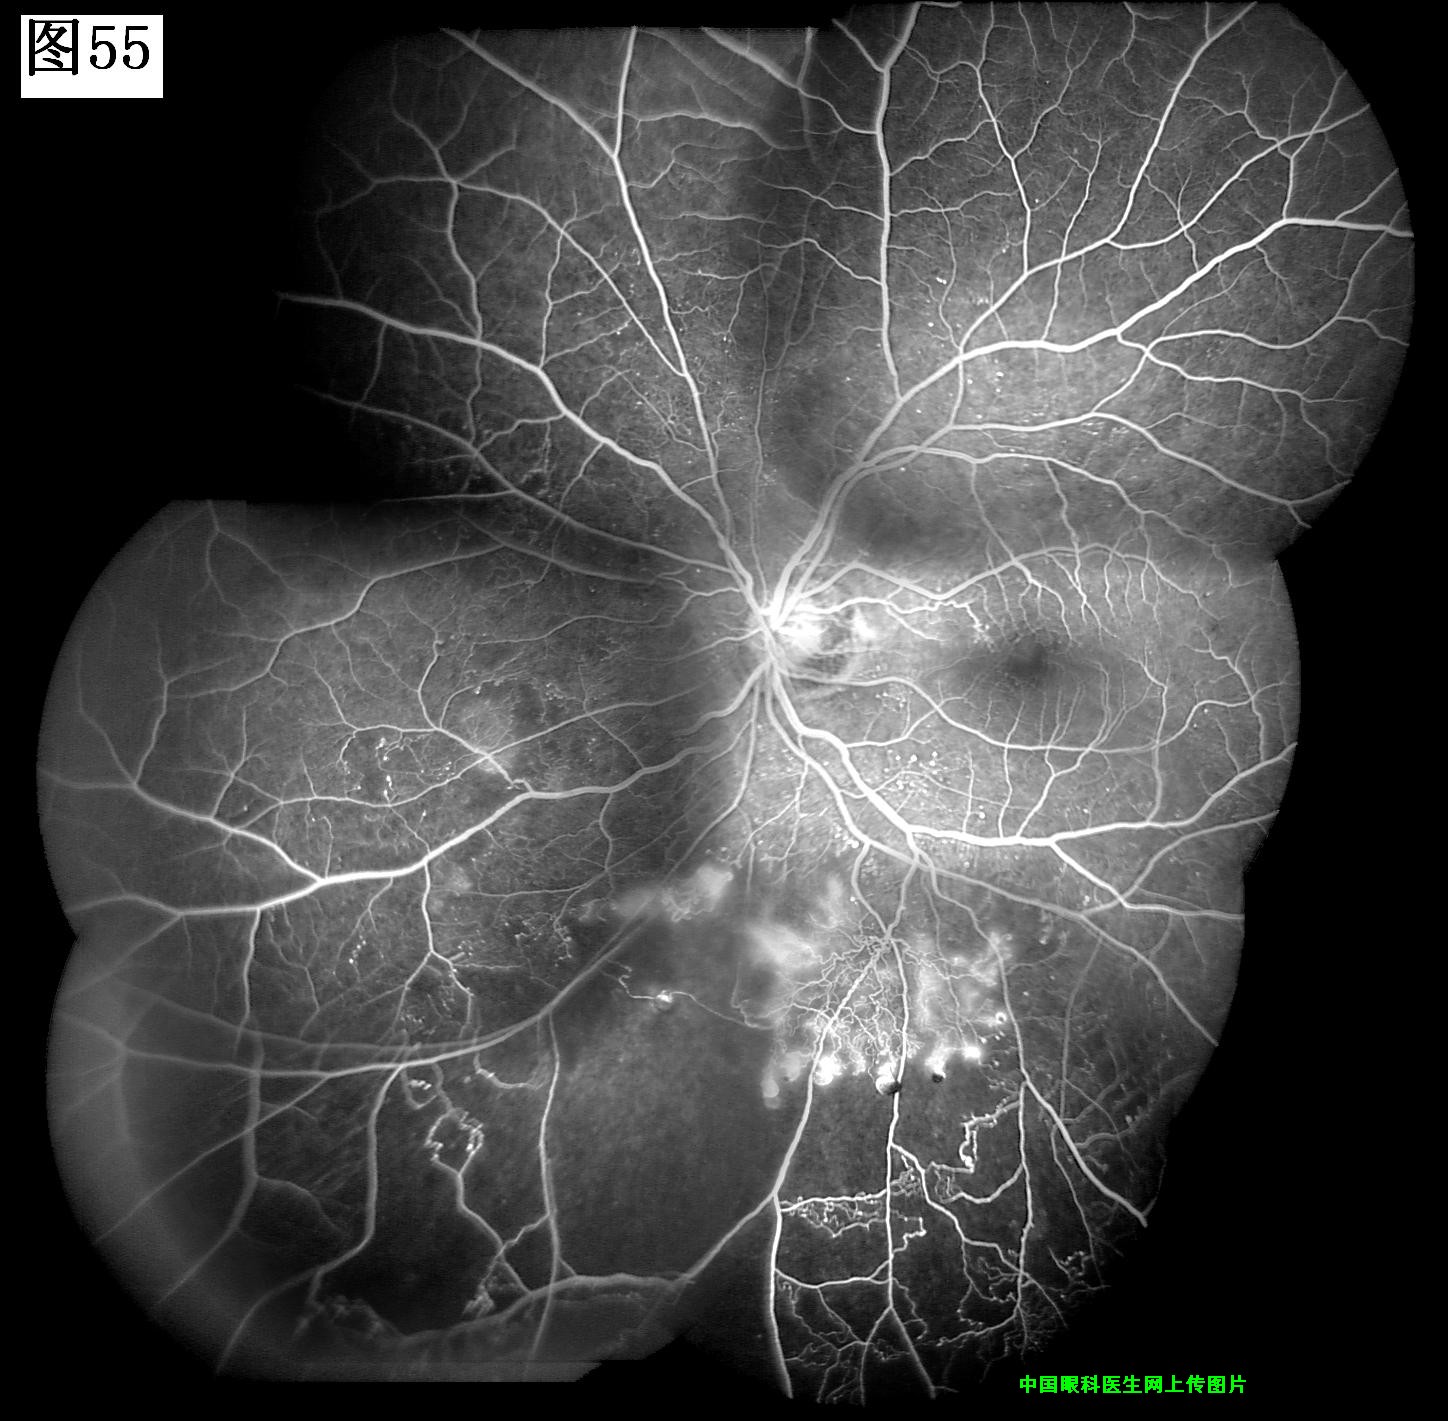

53 54 55 56